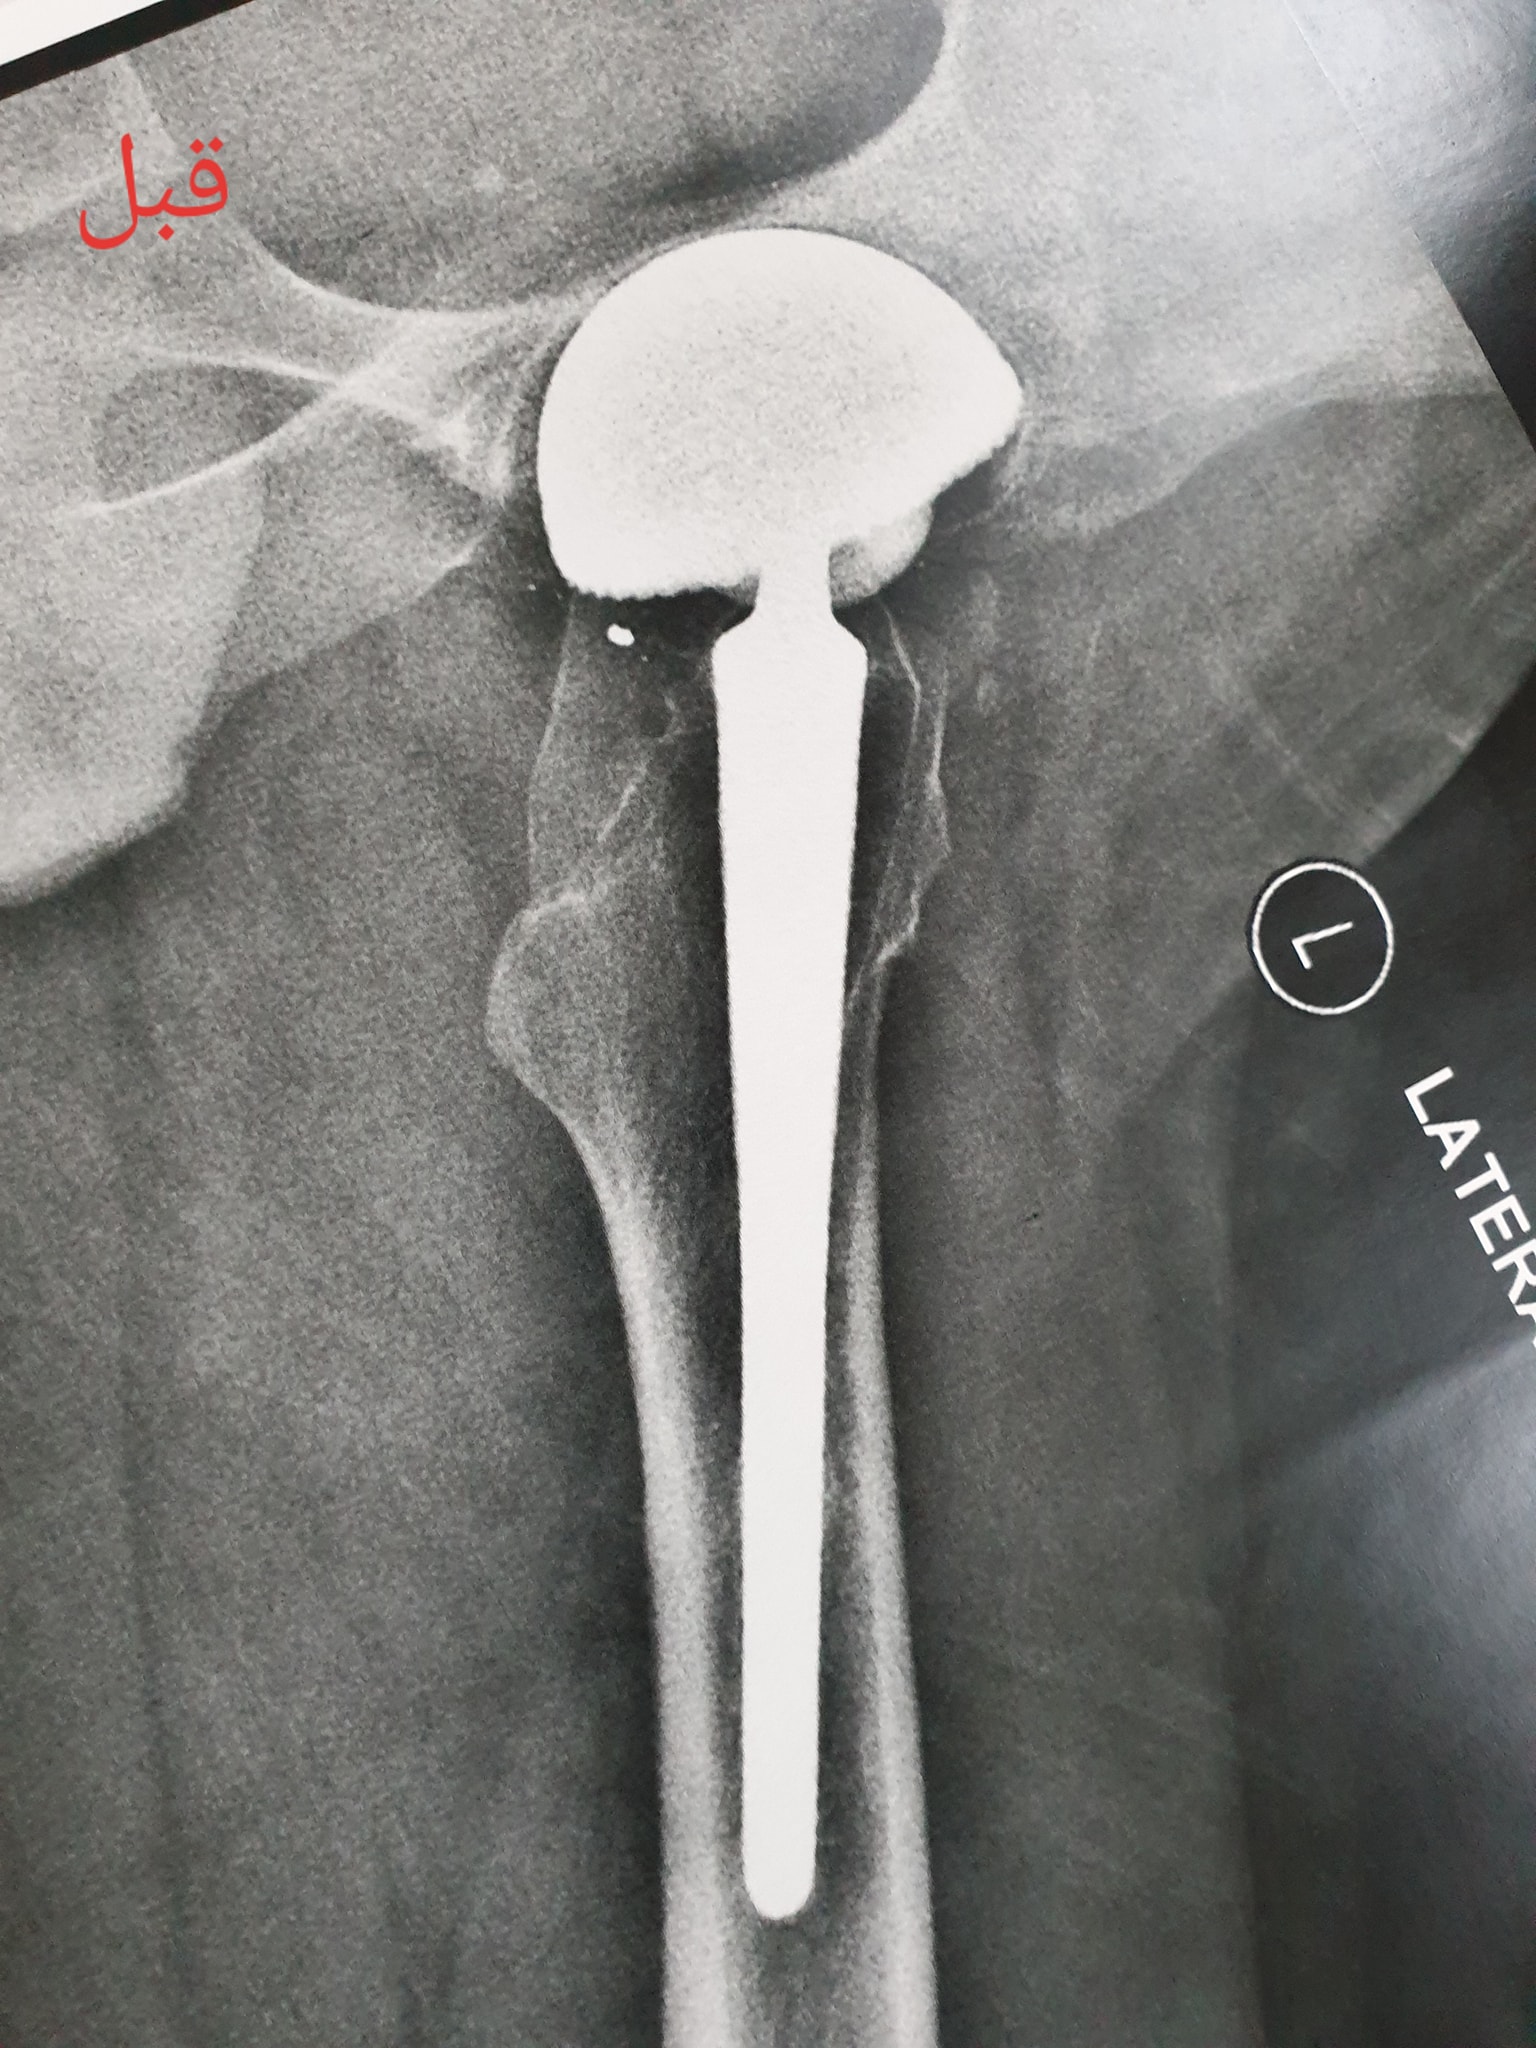

زراعة المفاصل الصناعية ورك و